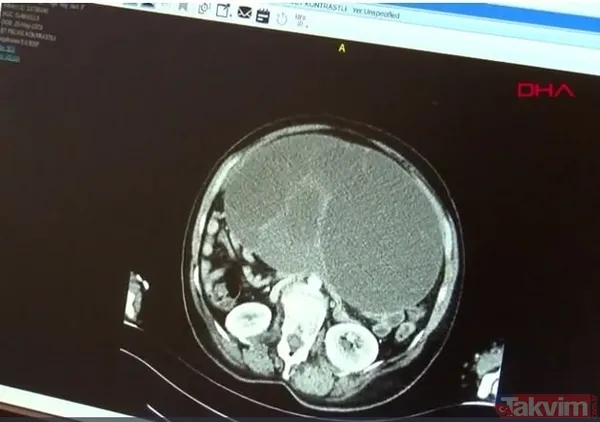

Karın şişliği ve kilo şikayeti nedeniyle Kayseri Şehir Hastanesi'ne gelen iki çocuk annesi Yeter Altıntaş'ın, yapılan muayene ve tahlillerin ardından yumurtalık bölgesine yakın bir yerde tümör olduğu saptandı.

Jinekoloji ve Onkoloji Cerrahisi Uzmanı Op. Dr. Seda Şahin Aker tarafından yapılan ameliyatta; Altıntaş'ın karnından 9 kilo ağırlığındaki tümör çıkartıldı.